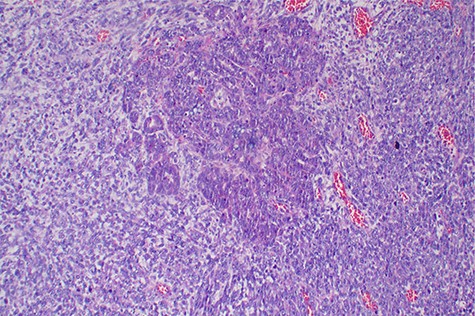

Histopathology of the tumor with malignant epithelial and sarcomatous elements, hematoxylin and eosin, ×100 magnifications.

Malignant mixed Müllerian tumor of the ovary is a rare tumor that accounts for ~1% of all ovarian cancers [1, 2]. These tumors are typically large, ranging from 10–20 cm in diameter; our patient’s tumor was 15.6 × 7.1 × 6.1 cm (Fig. 3). The presence of an intimate admixture of malignant epithelial and stromal elements (Figs 4, 5) is the morphological characteristic feature of this tumor. The epithelial element is most commonly a high-grade serous or endometrioid carcinoma, but can be of any of the surface epithelial cell types of ovarian tumors. The stromal component usually contains sheets of hyperchromatic rounded to spindled cells with marked nuclear atypia and a high mitotic index (Fig. 5). Immunohistochemical stains for epithelial markers are often positive in the sarcomatous component, as it has been observed in the index case (Fig. 6), and their behavior and patterns of spread are similar to high-grade serous carcinomas [3–5].